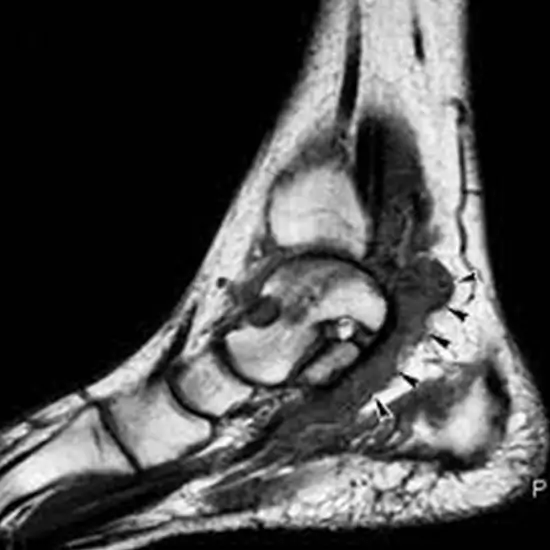

MRI screening of the heel is a non-invasive diagnostic tool used to look for abnormalities in the heel. It can be an effective tool for treating and diagnosing heel pain, allowing clinicians to see beneath the surface, literally.

MRI can also diagnose the following conditions: plantar heel discomfort, foot and ankle problems, and neuropathy.

• Injuries such as tendons, ligaments, and cartilage

• Fractures

• Tumours and infections

• Delayed union of fractured bones

MRI (Magnetic Resonance Imaging) screening of the heel is a non-invasive radiology test used to evaluate the condition of the heel and surrounding tissue. MRI Screening of the heel is done to look for its condition and surrounding area.